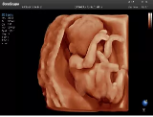

容積探頭是在二維圖像的基礎(chǔ)上,將連續(xù)采集的空間分布位置,經(jīng)過計算機(jī)重建算法,從而獲得完整的空間形態(tài)。

適用于:胎兒面部、脊柱和肢體等。

優(yōu)勢特點:快速獲取、掃查連續(xù)均勻、解剖結(jié)構(gòu)顯示為容積數(shù)據(jù)、準(zhǔn)確進(jìn)行容積測量。